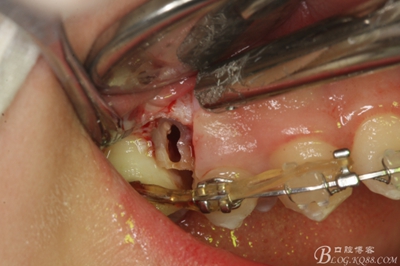

圖15 .微創(chuàng)挺把15牙根縱分成近遠(yuǎn)中兩塊

圖16.微創(chuàng)挺挺松近中根面部分,從16與14之間間隙出來

圖17.血管鉗取出近中部分15牙根